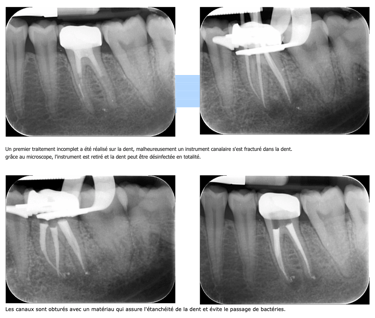

Quand le premier traitement réalisé n’est pas satisfaisant, un retraitement est à envisager afin de traiter ou prévenir la formation d'un kyste.

Ce type de lésion osseuse apparait, lorsqu'une petite partie du canal n'est pas désinfectée et obturée. Il est indispensable que tout le volume canalaire de la dent soit nettoyé et obturé.

Après avoir éliminé le matériau d’obturation existant et après avoir contourné les différents obstacles (démontage des prothèses et/ou des tenons, suppression des fragments d’instruments fracturés dans le canal, récupération des trajectoires canalaires, etc…), tous les canaux sont à nouveau nettoyés, désinfectés et obturés.